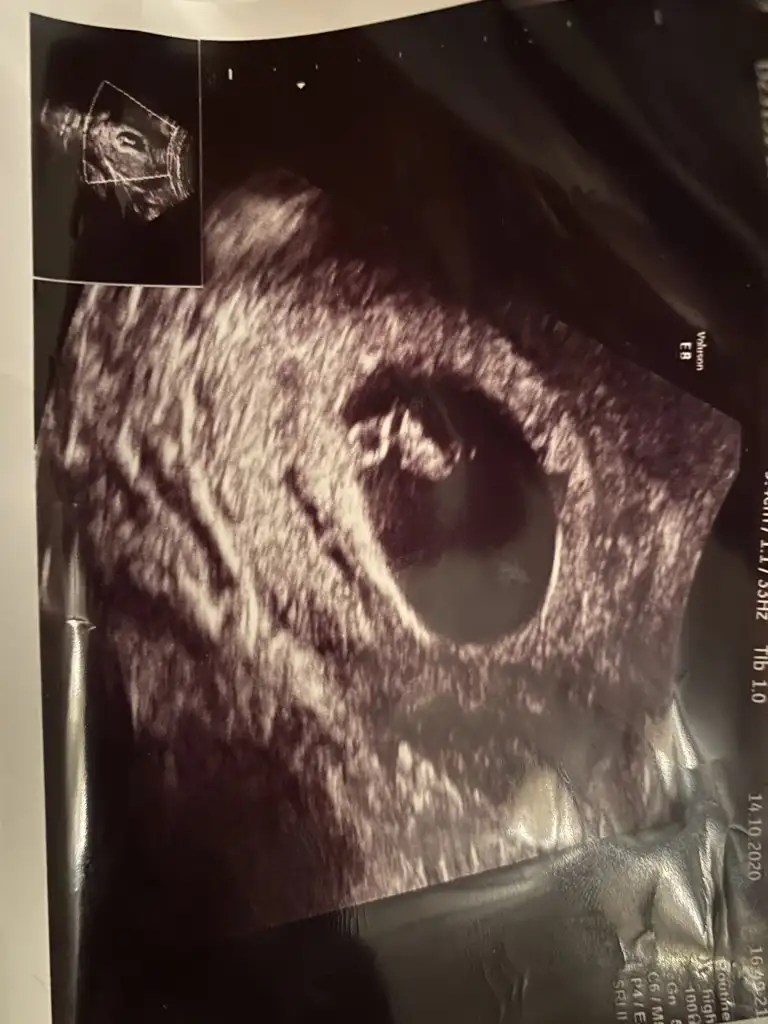

Ikra meyra bilio ona sor cnmTeyzeleri cinsiyet tahmının de bulunabılır mısınızKarın ultrasonu 12+1 günlük

Ultrason kagidinda 14 haftalik goruluyor siz 12 demissiniz. Bebiste buyuk baya 12 haftadan buyuk duruyorTeyzeleri cinsiyet tahmının de bulunabılır mısınızKarın ultrasonu 12+1 günlük

Ne olur bu ikinci yerden yazışım benimki küçücük daha ama çoooook merak ediyorum 1. Foto vajinal bakıldı 6. Haftalarda sadece yolk sacı görünüyor denildi 2. Foto 7. Haftalarda karından bakıldı bi tahmin yapın lütfen tabiyki sağlıklı olsun hayırlı evlat hayırlu kul olsun ama işte merak öldürüyor insanı sizi gördüğüm yere yazıyorum bunuKız gibi sanki net değil başka USG varsa paylaşın

Erkek buna göre en iyi 11 12 13 haftalar olmalıNe olur bu ikinci yerden yazışım benimki küçücük daha ama çoooook merak ediyorum 1. Foto vajinal bakıldı 6. Haftalarda sadece yolk sacı görünüyor denildi 2. Foto 7. Haftalarda karından bakıldı bi tahmin yapın lütfen tabiyki sağlıklı olsun hayırlı evlat hayırlu kul olsun ama işte merak öldürüyor insanı sizi gördüğüm yere yazıyorum bunu